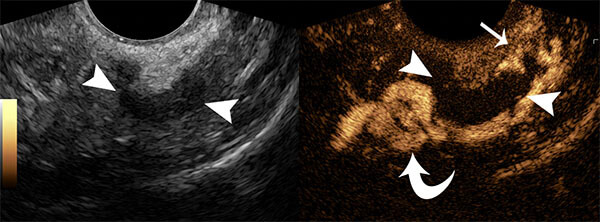

- Contrast hysterosalpingography: Ultrasound imaging of the uterus and fallopian tubes after filling these structures with contrast material. This allows assessment for tubal obstruction.

- The radiologist will insert a speculum into the vagina, clean the cervix and insert a catheter into the uterus. The speculum is then removed, and an ultrasound transducer (the “camera”) is inserted into the vagina. Saline then contrast material is infused through the catheter while imaging with ultrasound.